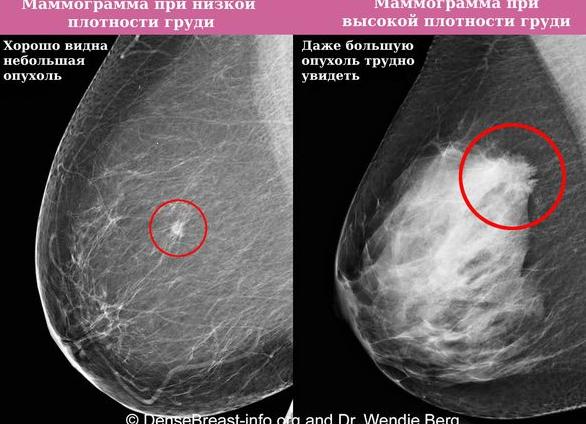

Для уточнения состояния груди женщинам назначают УЗИ (оптимальный метод до 35–40 лет) либо маммографию (рентгенографию груди проводят после сорока и в сложных случаях патологий у молодых женщин). При выявлении патологических изменений маммолог дополнительно назначает термографию, МРТ, дуктографию.

На маммограммах инволютивные изменения молочной железы с фиброзом определяются уже в 35 – 40-летнем возрасте. Они вначале проявляются уменьшением железистой ткани долек и замене ее жировой тканью, появлением многочисленных фиброзных тяжей между долек (междольковый фиброз), распространением разрастания соединительной ткани вдоль мелких, а затем и крупных молочных протоков (перидуктальный фиброз молочной железы), в результате чего протоки сдавливаются и постепенно запустевают. Впоследствии дольки полностью заменяются жировой тканью, которая преобладает над соединительнотканным компонентом.